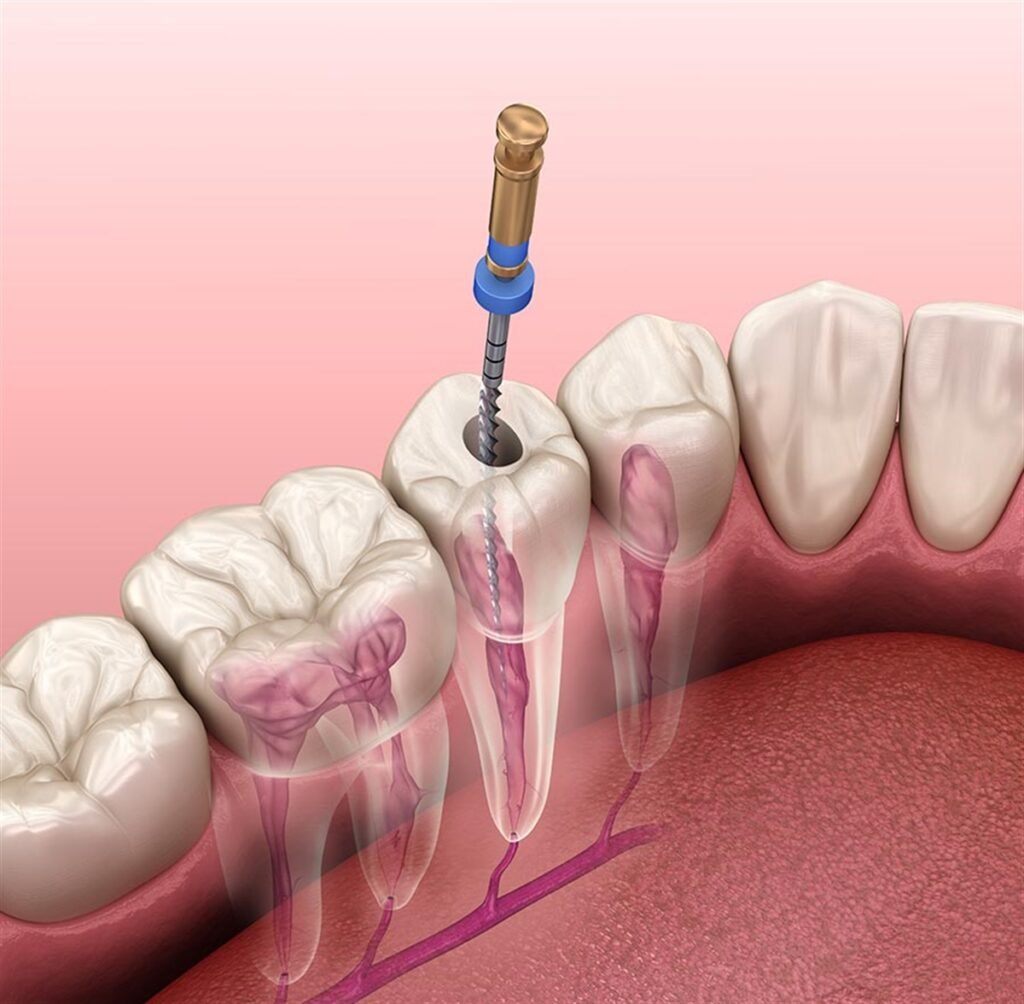

Endodontik Tedavi (Kök Kanal Tedavisi)